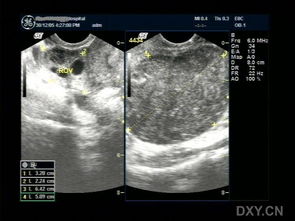

不知道您說(shuō)的子宮左側是宮腔內的腫塊還是附件的腫塊,如果是子宮腔內的那么就是子宮肌瘤,而且肌瘤已經(jīng)相對較大了,需要早期的手術(shù)治療,建議您可以根據肌瘤的具體位置選擇合適的手術(shù)方法,粘膜下和肌壁間肌瘤采用奧洛克超導多彈頭系統治療,這種方法不需要開(kāi)刀不需要住院,損傷小,腹部沒(méi)有任何瘢痕,可以保留子宮和生育能力,如果是漿膜下建議采用宮腹腔鏡方法治療,如果是附件的囊腫,那么也建議早期手術(shù),以免劇烈活動(dòng)會(huì )引起囊腫的扭轉發(fā)生大出血,囊腫的治療首先需要確診囊腫的性質(zhì),可以采用奧洛克導航微電極系統或者腹腔鏡方法治療,詳細的情況建議您先確診具體是什么情況,然后選擇合適的治療方法,祝您早日康復!